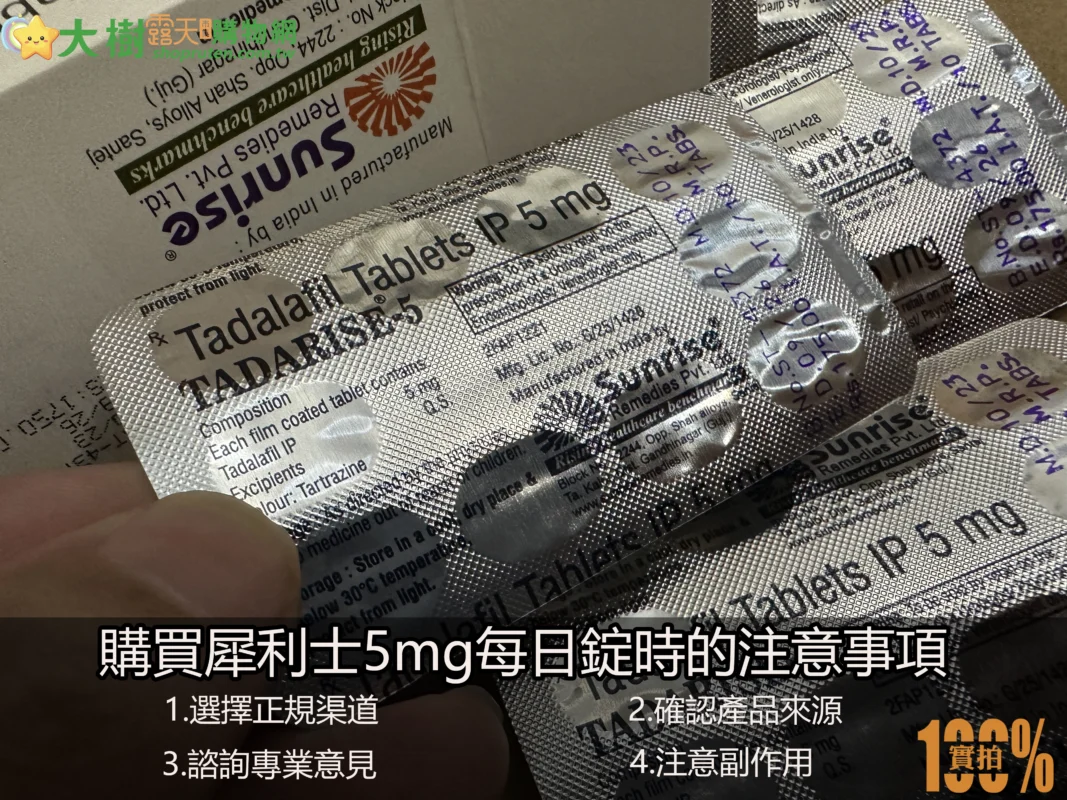

購買犀利士5mg注意事項

- 選擇正規渠道:無論是網購、實體藥局還是代購,都應選擇信譽良好的平台,避免因貪圖便宜而購買到假貨或劣質藥物。

- 確認產品來源:犀利士5mg每日錠的主要生產地是印度和美國,購買時務必確認產品的包裝、標識及認證標誌,確保所購產品為正品。

- 諮詢專業意見:由於犀利士5mg每日錠適合長期服用,因此在使用前應先諮詢專業醫師或藥師,了解適合的劑量和用法。

- 注意副作用:犀利士5mg每日錠可能引發頭痛、面部潮紅、胃部不適等副作用,服用後如有不適,應立即停止並尋求醫療建議。